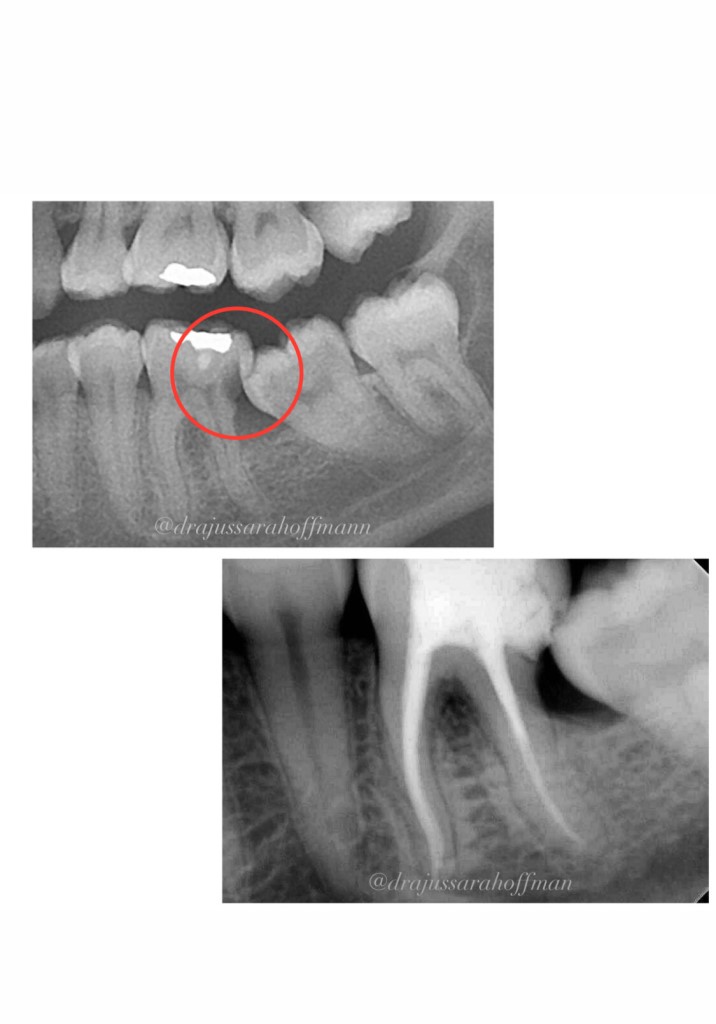

Endodontia

A Endodontia (tratamento de Canal) é a especialidade que trata o sistema de canais radiculares. Todos os dentes possuem uma estrutura no interior da raiz, chamada de polpa (canal), ela é a responsável por toda a nutrição do dente.

O tratamento de canal é uma das opções para salvar os dentes quando estes são acometidos por cáries profundas ou alguma patologia mais séria.

Aqui na clínica ARPE, o especialista atende os pacientes utilizando os mais modernos equipamentos como por exemplo, ultrassom, motor rotatório e reciprocante, localizador apical (instrumento que localiza com precisão o espaço ocupado pela polpa do dente), radiografia digital, entre outros equipamentos e materiais, tudo isso para garantir um tratamento seguro, com o objetivo de sanar a dor e a infecção.